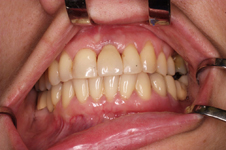

Bezzubá čelist je hlavní indikací pro ošetření pomocí implantátů. Zejména celkové zubní náhrady v dolní čelisti mají velice nízkou stabilitu a držení díky velkému úbytku kosti.

S pomocí zubních implantátů můžeme díky různým kotevním systémům (třmeny, kulové hlavy, Locatory) zajistit stabilitu a držení protézy nebo při použití většího počtu implantátů zhotovit pevné náhrady – můstky nalepené nebo našroubované na pevno na implantáty.

S těmito typy náhrad můžeme dosáhnout perfektní funkci, výbornou estetiku, fonetiku a současně zajistit u pacienta možnost dobré hygienickou péče a čištění, která je pro životnost implantátů velice důležitá.